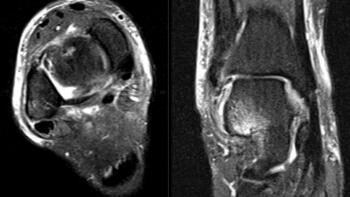

Her initial injury radiographs revealed a small lucent area of the talar dome consistent with an osteochondral defect. Radiographs three months later revealed a more distinct osteochondral defect with a detached fragment of the lateral dome. The MRI was consistent with the radiographs, showing the detached fragment, corresponding bone edema and lateral ligament injury.

New radiographs revealed a small lucent area of the lateral talar dome but no loose body or fragment. Treatment included non-steroidal anti-inflammatory drugs (NSAIDs) and bracing. A month later with no relief, we ordered a new MRI, which revealed an increased number of cystic changes to the lateral talar dome. There was no loose fragment and the cyst areas appeared contained, but it now involved a large area.